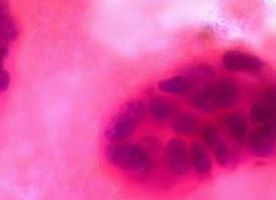

Scientists have discovered new types of immature cells in mammary glands, uncovering clues to the origins of different breast cancers - and potential new drug targets, according to findings published in Breast Cancer Research.

The team at Cancer Research UK’s Cambridge Research Institute identified at least two types of immature cells, called progenitor cells. Unlike stem cells, which can develop into any type of cell and keep on dividing, progenitor cells can only divide a limited number of times.

Cancer is thought to begin in cells that can produce many daughter cells, which form the tumour mass. So different progenitor cells may explain why there are different types of breast cancer.

The team discovered that one group of progenitor cells, called oestrogen positive progenitors, had oestrogen receptors. This protein receives signals from the sex hormone, oestrogen. The other group - oestrogen negative cells - lacked this receptor.